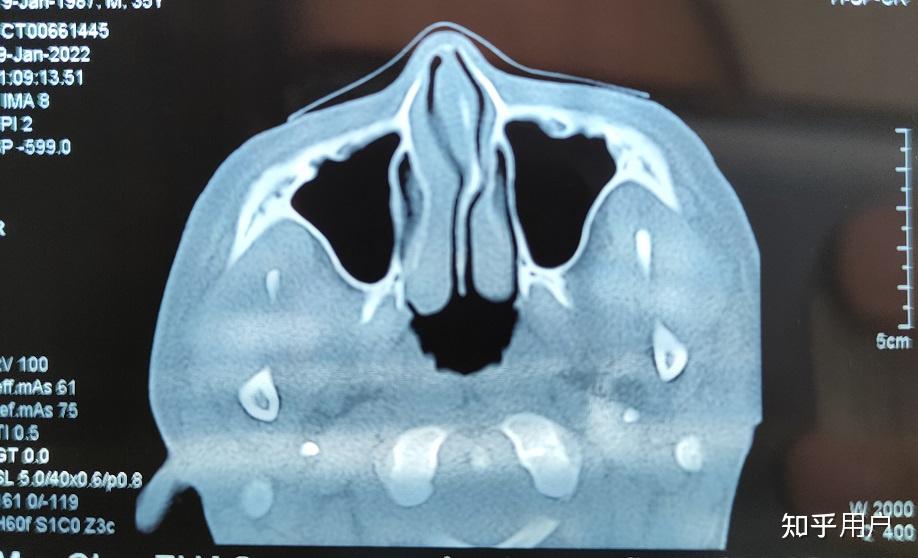

91中隔偏曲指软骨向一侧或两侧弯曲98或鼻中隔一侧或两侧局部突起

鼻中隔偏曲

鼻中隔偏曲解析图